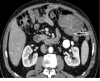

Figure 3. Case 1. Contrast-enhanced abdominal CT scan

This shows a well-defined homogenous non-adipocytic round mass in the mesentery close to the staple line of the ileocolic anastomosis (red arrow).